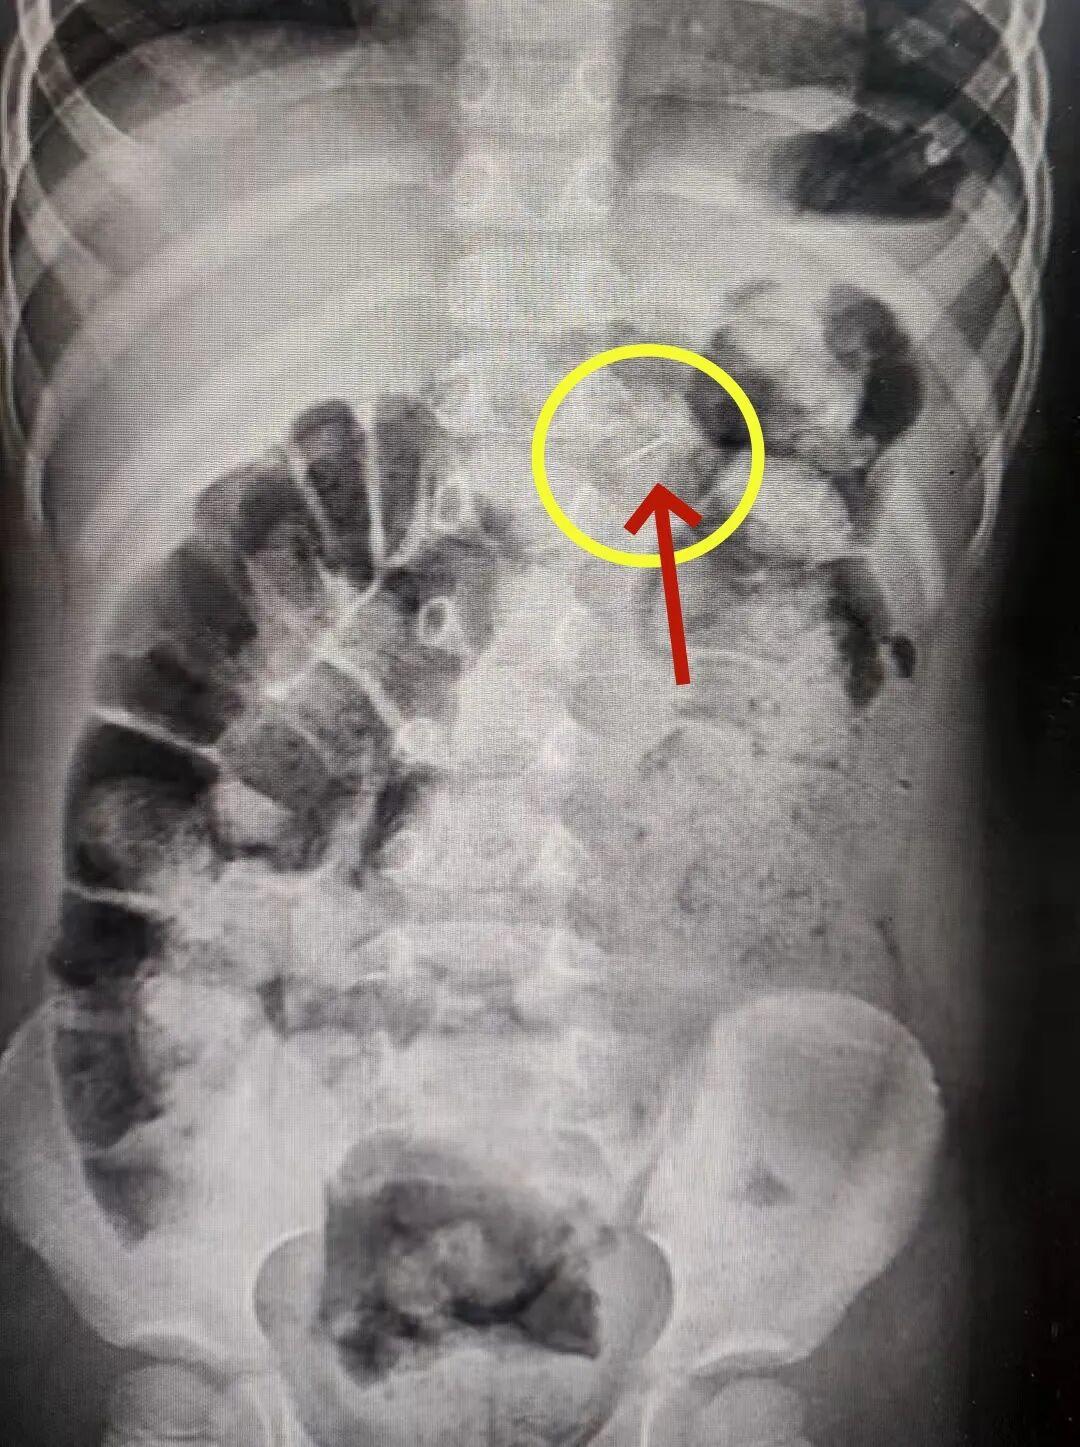

接诊医生高度警惕,第一时间安排影像学检查。片子清晰显示胃内一枚针状异物。

急诊科医生紧急联系消化内科医生进行进一步的判断:胃肠粘膜很薄,肠壁也很薄,尖锐断针可能会随着胃蠕动进入肠内导致穿孔。情况危急,必须连夜手术取出!